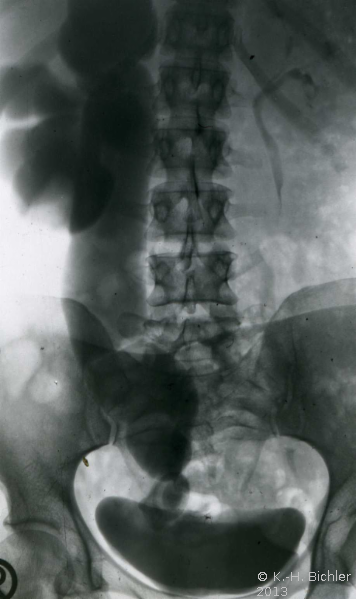

Die Ureterozele kann auch trotz Komplikationen (Harnsteinbildung) und schwersterster Abflussbehinderung lange Zeit unerkannt bleiben (rezidivierende Harnwegsinfekte) wie bei dieser Erwachsenen mit sekundärem Megaureter bei steintragender Ureterozele rechts und rezidivierendem Harnwegsinfekt (Abbildung 3) (

KasuistikKasuistikBei dieser 54jährigen Frau fand sich ein sekundär-obstruktiver Megaureter bei Ureterozele mit Harnsteinbildung. Jahrelang rezidivierende Harnwegsinfekte ohne entsprechende Abklärung. Therapie: Schlitzung der Ureterozele und Harnsteinentfernung (s. Abbildung 3).).